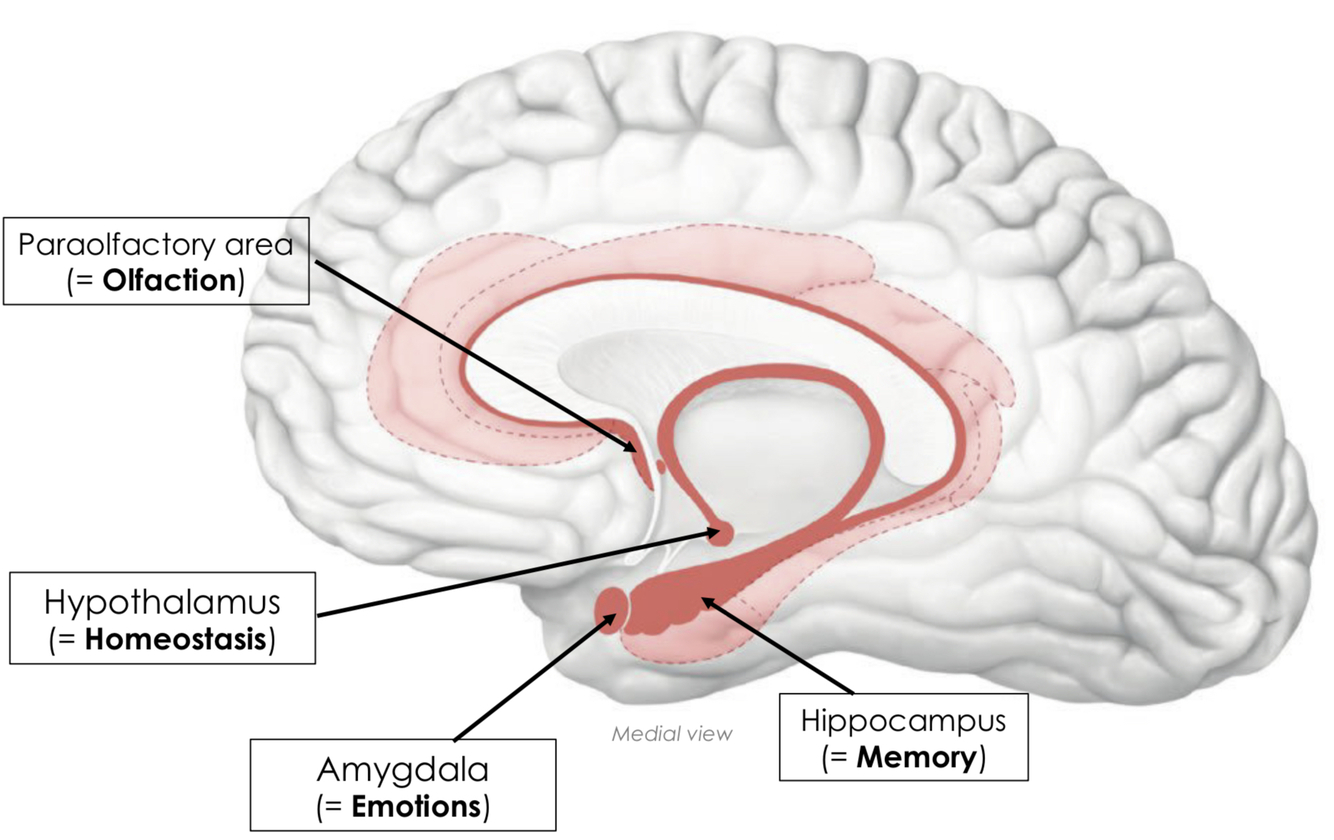

What is meant by HOME to remember the limbic structures?

H - Homeostasis

- performed by the hypothalamus

- e.g. blood pressure, heart rate, production and release of hormones

O - Olfaction

- paraolfactory area

M - Memory

- hippocampus

E - Emotions

- amygdala